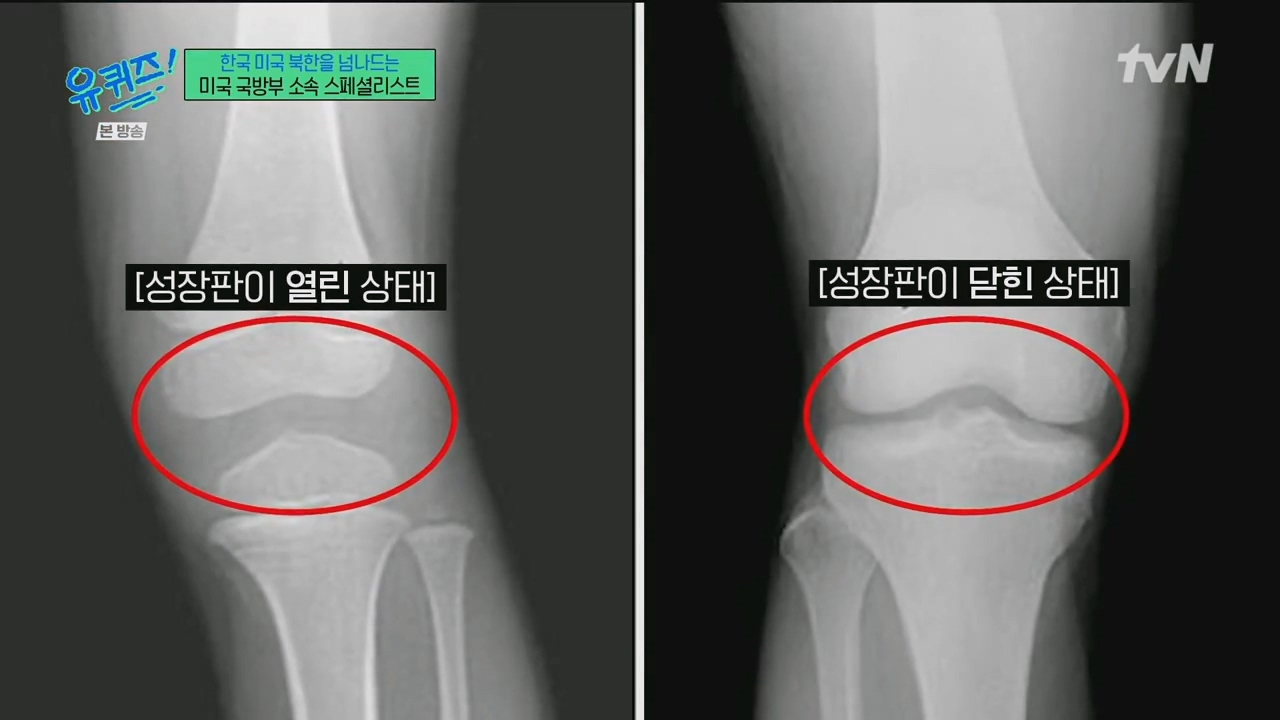

6.25ÀüÀï »ç¸ÁÀÚ À¯ÇØ ºÐ¼®Çؼ °¡Á·¿¡°Ô º¸³»ÁÖ´Â ¹Ì±¹ ±¹¹æºÎ ¼Ò¼Ó ¹ýÀÇÀηùÇÐÀÚ